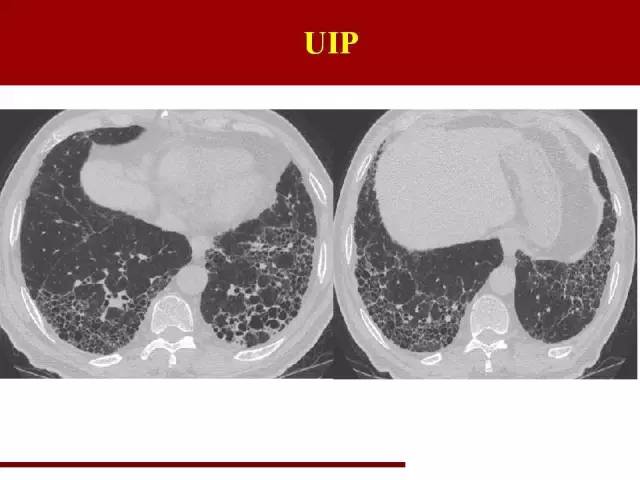

寻常型间质性肺炎UIP

下面是这几类病变的影像特点

红字是主要特点,蓝字是必须排除的要点

影像特点大家应该都很熟悉,但是少有人注意需要排除的条件

这点在诊断的过程中必须注意

双肺中下肺野胸膜下分布、网格状阴影多于磨玻璃阴影,终末期可以有蜂窝肺形成,伴有牵拉性支气管扩张